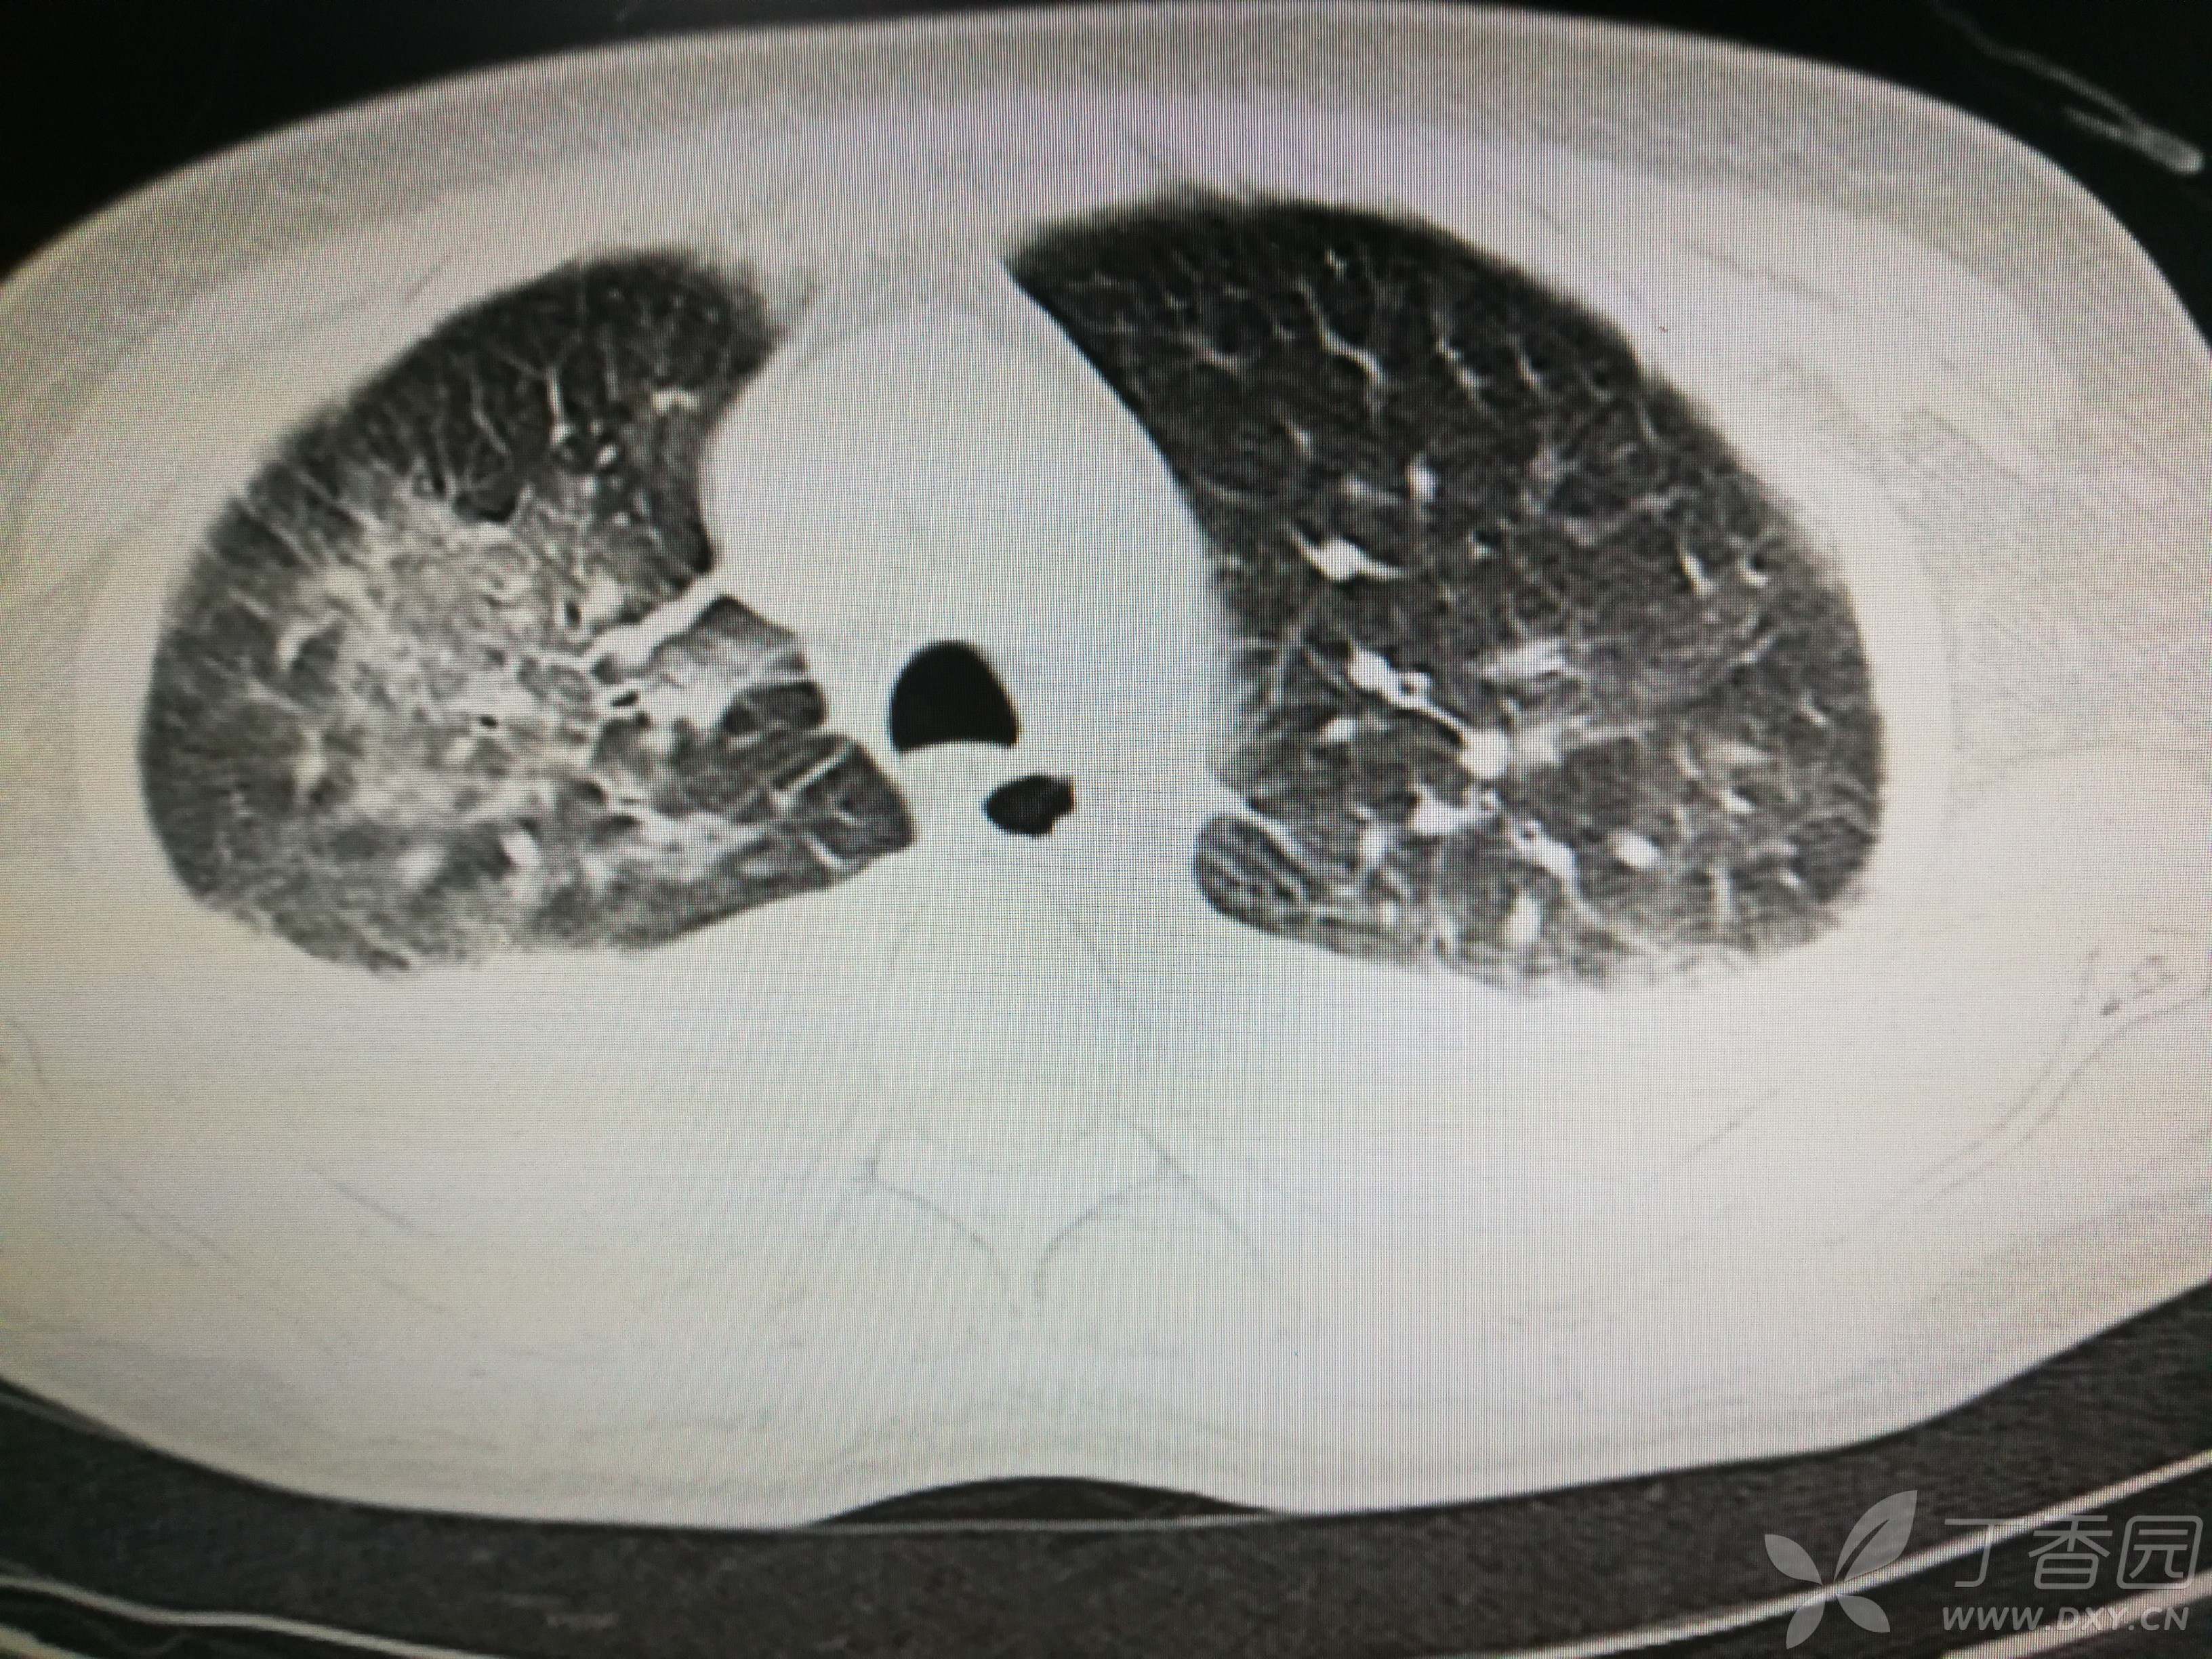

给予低分子肝素钙针抗凝、七叶皂苷钠针消肿及骨牵引固定等等治疗。入院后第四天行“左侧股骨下段骨折切开复位内固定术”(术前查双下肢彩超:双下肢深静脉血流通畅),手术顺利,术后予预防感染、预防血栓形成等治疗。术后患者无明显发热,生命体征平稳。术后第四天复查血常规:白细胞13.4×109/L,血红蛋白84g/L,血小板在正常范围。生化:白蛋白35.7g/L,余无明显异常。当天,患者开始出现轻度胸闷气急,可耐受。术后第五天患者胸闷气急加重,无胸痛,无背痛,无咯血,无意识障碍,无头晕头痛,无恶心呕吐等,急查凝血功能:纤维蛋白原降解产物12mg/L,D二聚体4000ug/L,余无明显异常。查动脉血气分析:pH7.52,氧分压62mmHg,二氧化碳分压30mmHg,碱剩余1.8mmol/L,乳酸1.0mm/L,血红蛋白86g/L。查胸部CT见下(先视频后图片):